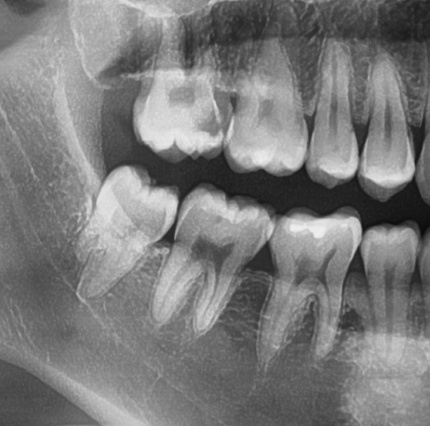

신경치료를 시작하게 되면서 내원 횟수가 최소 3회 이상으로 늘어나게 되었고..

성공적인 신경치료 후에는 반드시 크라운을 씌워야 하기 때문에 비용 또한 늘어나게 되었습니다.

모 유튜브를 보면 크라운이 과잉치료다 라는 책임 없는 말을 하시는 분들이 있는데..

어금니 부위는 신경치료 후 반드시 치아 보호를 위해 크라운을 씌워 주어야

추 후, 치아가 부러져서 발치하는 경우를 예방할 수 있습니다.

치아에 이미 신경치료를 위한 적절한 구멍을 내고,

나중에 빈 공간을 레진이라는 치과 재료로 메우게 되는데

어금니가 씹는 힘을 망가진 치아구조+레진이 견딜수가 없기 때문에

결국 신경치료 후 크라운을 하지 않은 어금니들은

가까운 시일 내에 부러져서 오는 경우가 매우 많습니다.